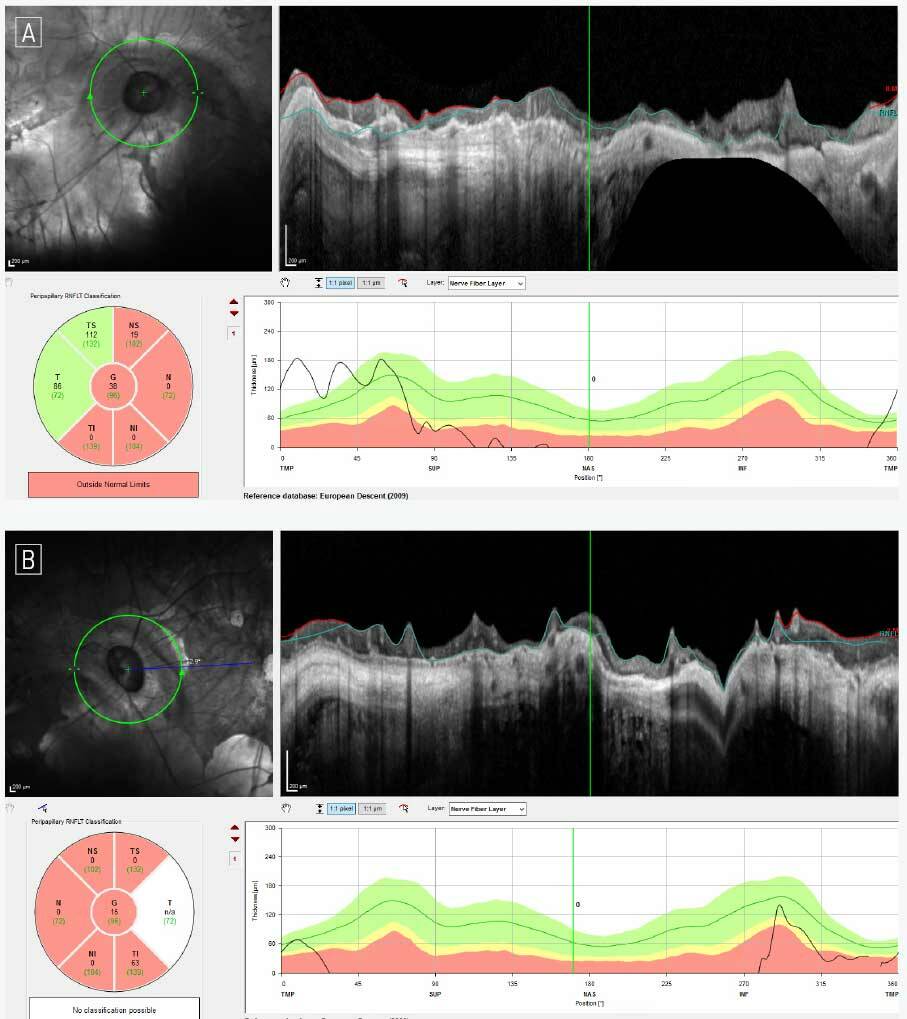

Diagnostic et suivi du glaucome du myope

Le glaucome chez le myope fort représente un défi diagnostique et thérapeutique en raison des altérations biomécaniques et morphologiques… Lire la suite